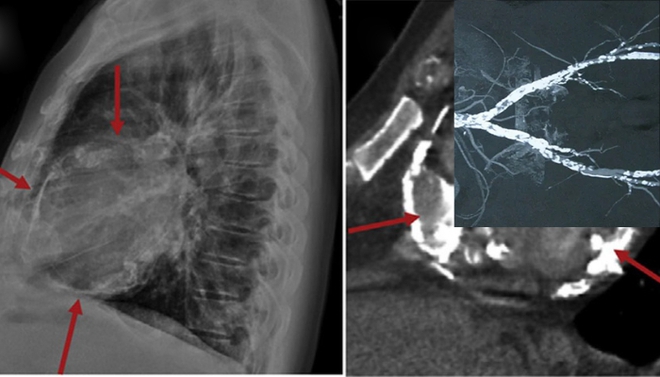

Tại đây, các bác sĩ nhanh chóng kiểm tra các chỉ số về thận của ông nhưng phát hiện vấn đề lần này không nằm ở thận. Dựa trên các triệu chứng lâm sàng, bác sĩ Jiang Shoushan tiến hành chụp X-quang phổi và mạch máu cho ông Chen. Kết quả là tuy không bị nhồi máu cơ tim giống như gia đình nghi ngờ nhưng những mạch máu ở tim của ông bị vôi hóa nghiêm trọng đến bất ngờ.

Bác sĩ Jiang chia sẻ về ca bệnh này trên chương trình “Cuộc sống khỏe mạnh và tốt đẹp” như sau: “Trong gần 20 năm hành nghề của mình, tôi rất hiếm gặp trường hợp mạch máu tim bị vôi hóa nghiêm trọng đến vậy ở độ tuổi đó. Khi nhìn vào hình ảnh X-quang, chính bệnh nhân cũng phải ngạc nhiên.

Bởi vì những mạch máu của ông đặc, cứng lại giống như ruột của chiếc bút chì. Do vậy, trên phim X-quang chúng trắng xóa và vô cùng rõ nét dù không dùng thuốc cản quang trước đó hay các máy móc hỗ trợ khác trong quá trình phân tích phim.